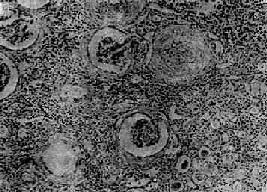

图12-25 慢性肾盂肾炎 有些肾小球毛细血管丛相对正常,肾球囊壁增厚,纤维化,部分肾小管萎缩消失,部分肾小管扩张,腔内有胶样管型;间质纤维组织增生,有大量淋巴细胞等炎细胞浸润 【临床病理联系】 慢性肾盂肾炎常反复急性发作。发作时症状与急性肾盂肾炎相似,尿中有多数白细胞、蛋白质和管型。由于肾小球损害发生较晚,肾小管病变比较严重,发生也较早,故肾小管功能障碍出现较早,也较明显。肾小管浓缩功能降低,可出现多尿和夜尿。电解质如钠、钾等和重碳酸盐丧失过多,可导致缺钠、缺钾和酸中毒。较晚期由于肾组织纤维化和小血管硬化,肾组织缺血,肾素分泌增加,通过肾素-血管紧张素的作用引起高血压。肾乳头萎缩,肾盂肾盏因瘢痕收缩而变形,可通过肾盂造影检见,对临床诊断有一定意义。晚期大量肾组织破坏,可引起氮质血症和尿毒症。 【结局】 慢性肾盂肾炎病程较长,及时治疗,可控制病变发展,肾功能可以得到代偿,不致引起严重后果。若病变广泛并累及双肾者,晚期可引起高血压和肾功能衰竭等严重后果,因此去除诱因和早期彻底治疗非常重要。